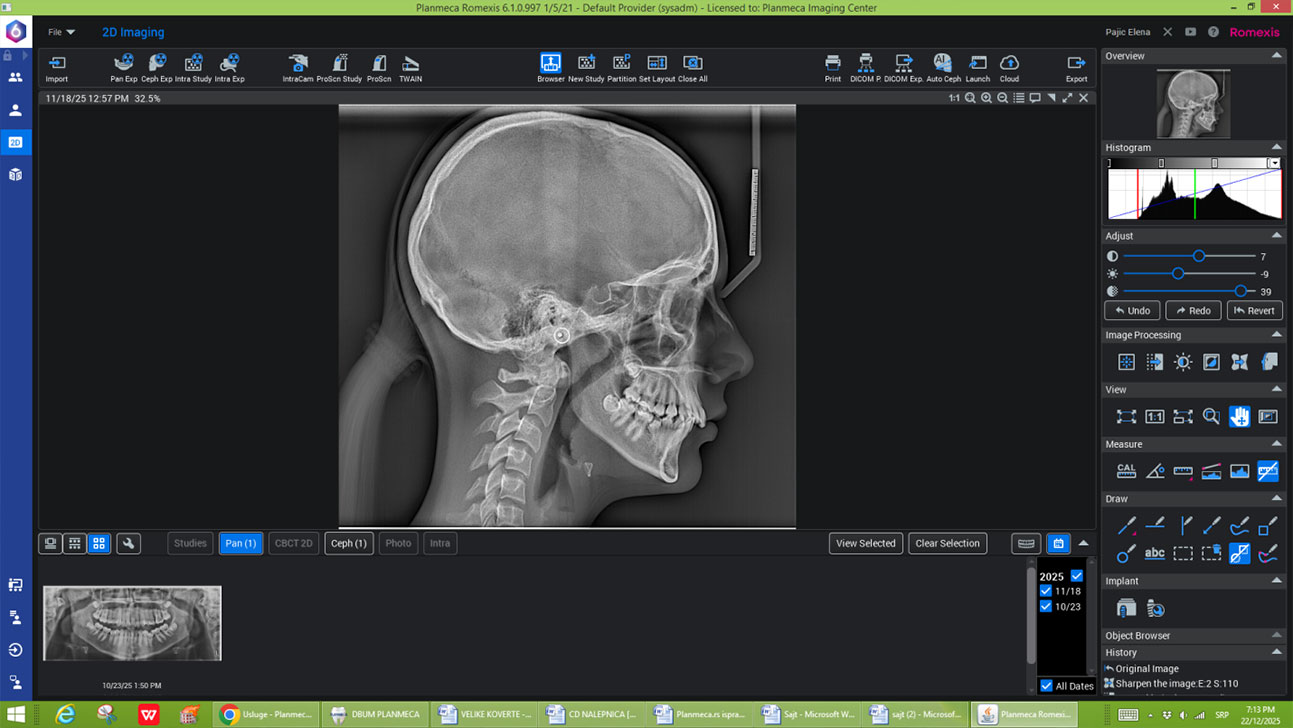

Programi za sinus, TMZ, cefalolometriju

2D - SNIMCI